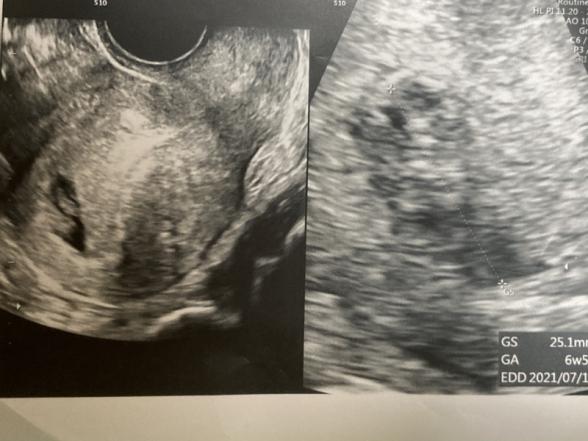

42歳、経産婦です。 妊娠反応があったので、今日病院に行ってきました。 胎嚢の大きさは25.1mで6週5日相当との事でしたが、心拍は確認出来ませんでした。 つわりらしきものは薄っすらと吐き気がたまにあるくらい、眠気がすごいくらいだったので覚悟はしていましたが、やはりショックでした。 何より、胎嚢が初めて見るくらいのいびつな形でした。 中には胎芽らしき何かがあるけど何なのかわからない、このまま流産になるかもしれないと言われました。 2週間後に診察がありますが、やはり胎嚢がこれだけいびつだと流産の可能性は高いのでしょうか? 今のところ、出血、腹痛はありません。

今すごく気になっているのは、胞状奇胎ではないかという事です。

血液検査もしていないので、エコー写真からは判断しにくいですが、その可能性があるから先生は、胎芽か何かわからないと言ったのかなと思い返しています。

助産師さんから見ても、やはり写真だけではわからないでしょうか?